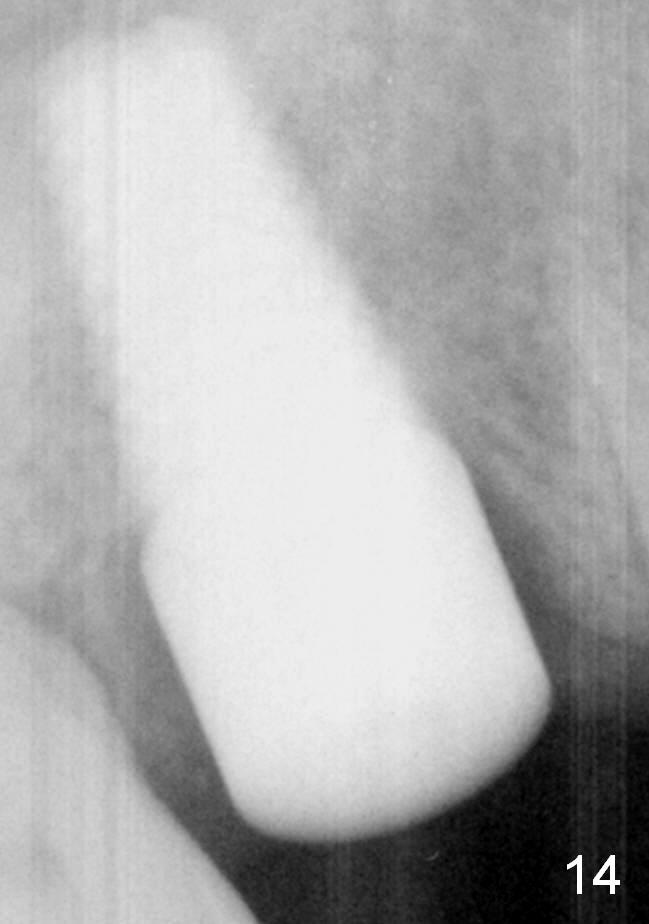

Fig.14: 23 months postop. The implant has osteointegrated apparently.